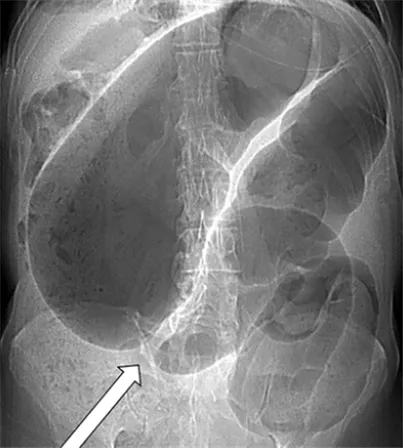

• cecal volvulus의 소견도 한 번 참고하시길 바랍니다.

특성 | Sigmoid volvulus | Cecal volvulus |

|---|---|---|

발생 위치 | 골반 (왼쪽 하복부) | 오른쪽 하복부 |

확장 방향 | 오른쪽 상복부 | 상복부 또는 왼쪽 상복부 |

외형 | Ahaustral(구조가 없는 모양) | Haustral pattern 유지 |

장 폐쇄 위치 | 하부 대장 폐쇄 | 보통 하부 대장은 붕괴됨 |

bowel dilatation | 상행, 횡행, 하행 대장이 확장될 수 있음 | 소장이 확장됨 |

air-fluid level | 몇 개의 air-fluid level 가능 | 하나의 air-fluid level 가능 |

▲ cecal volvulus